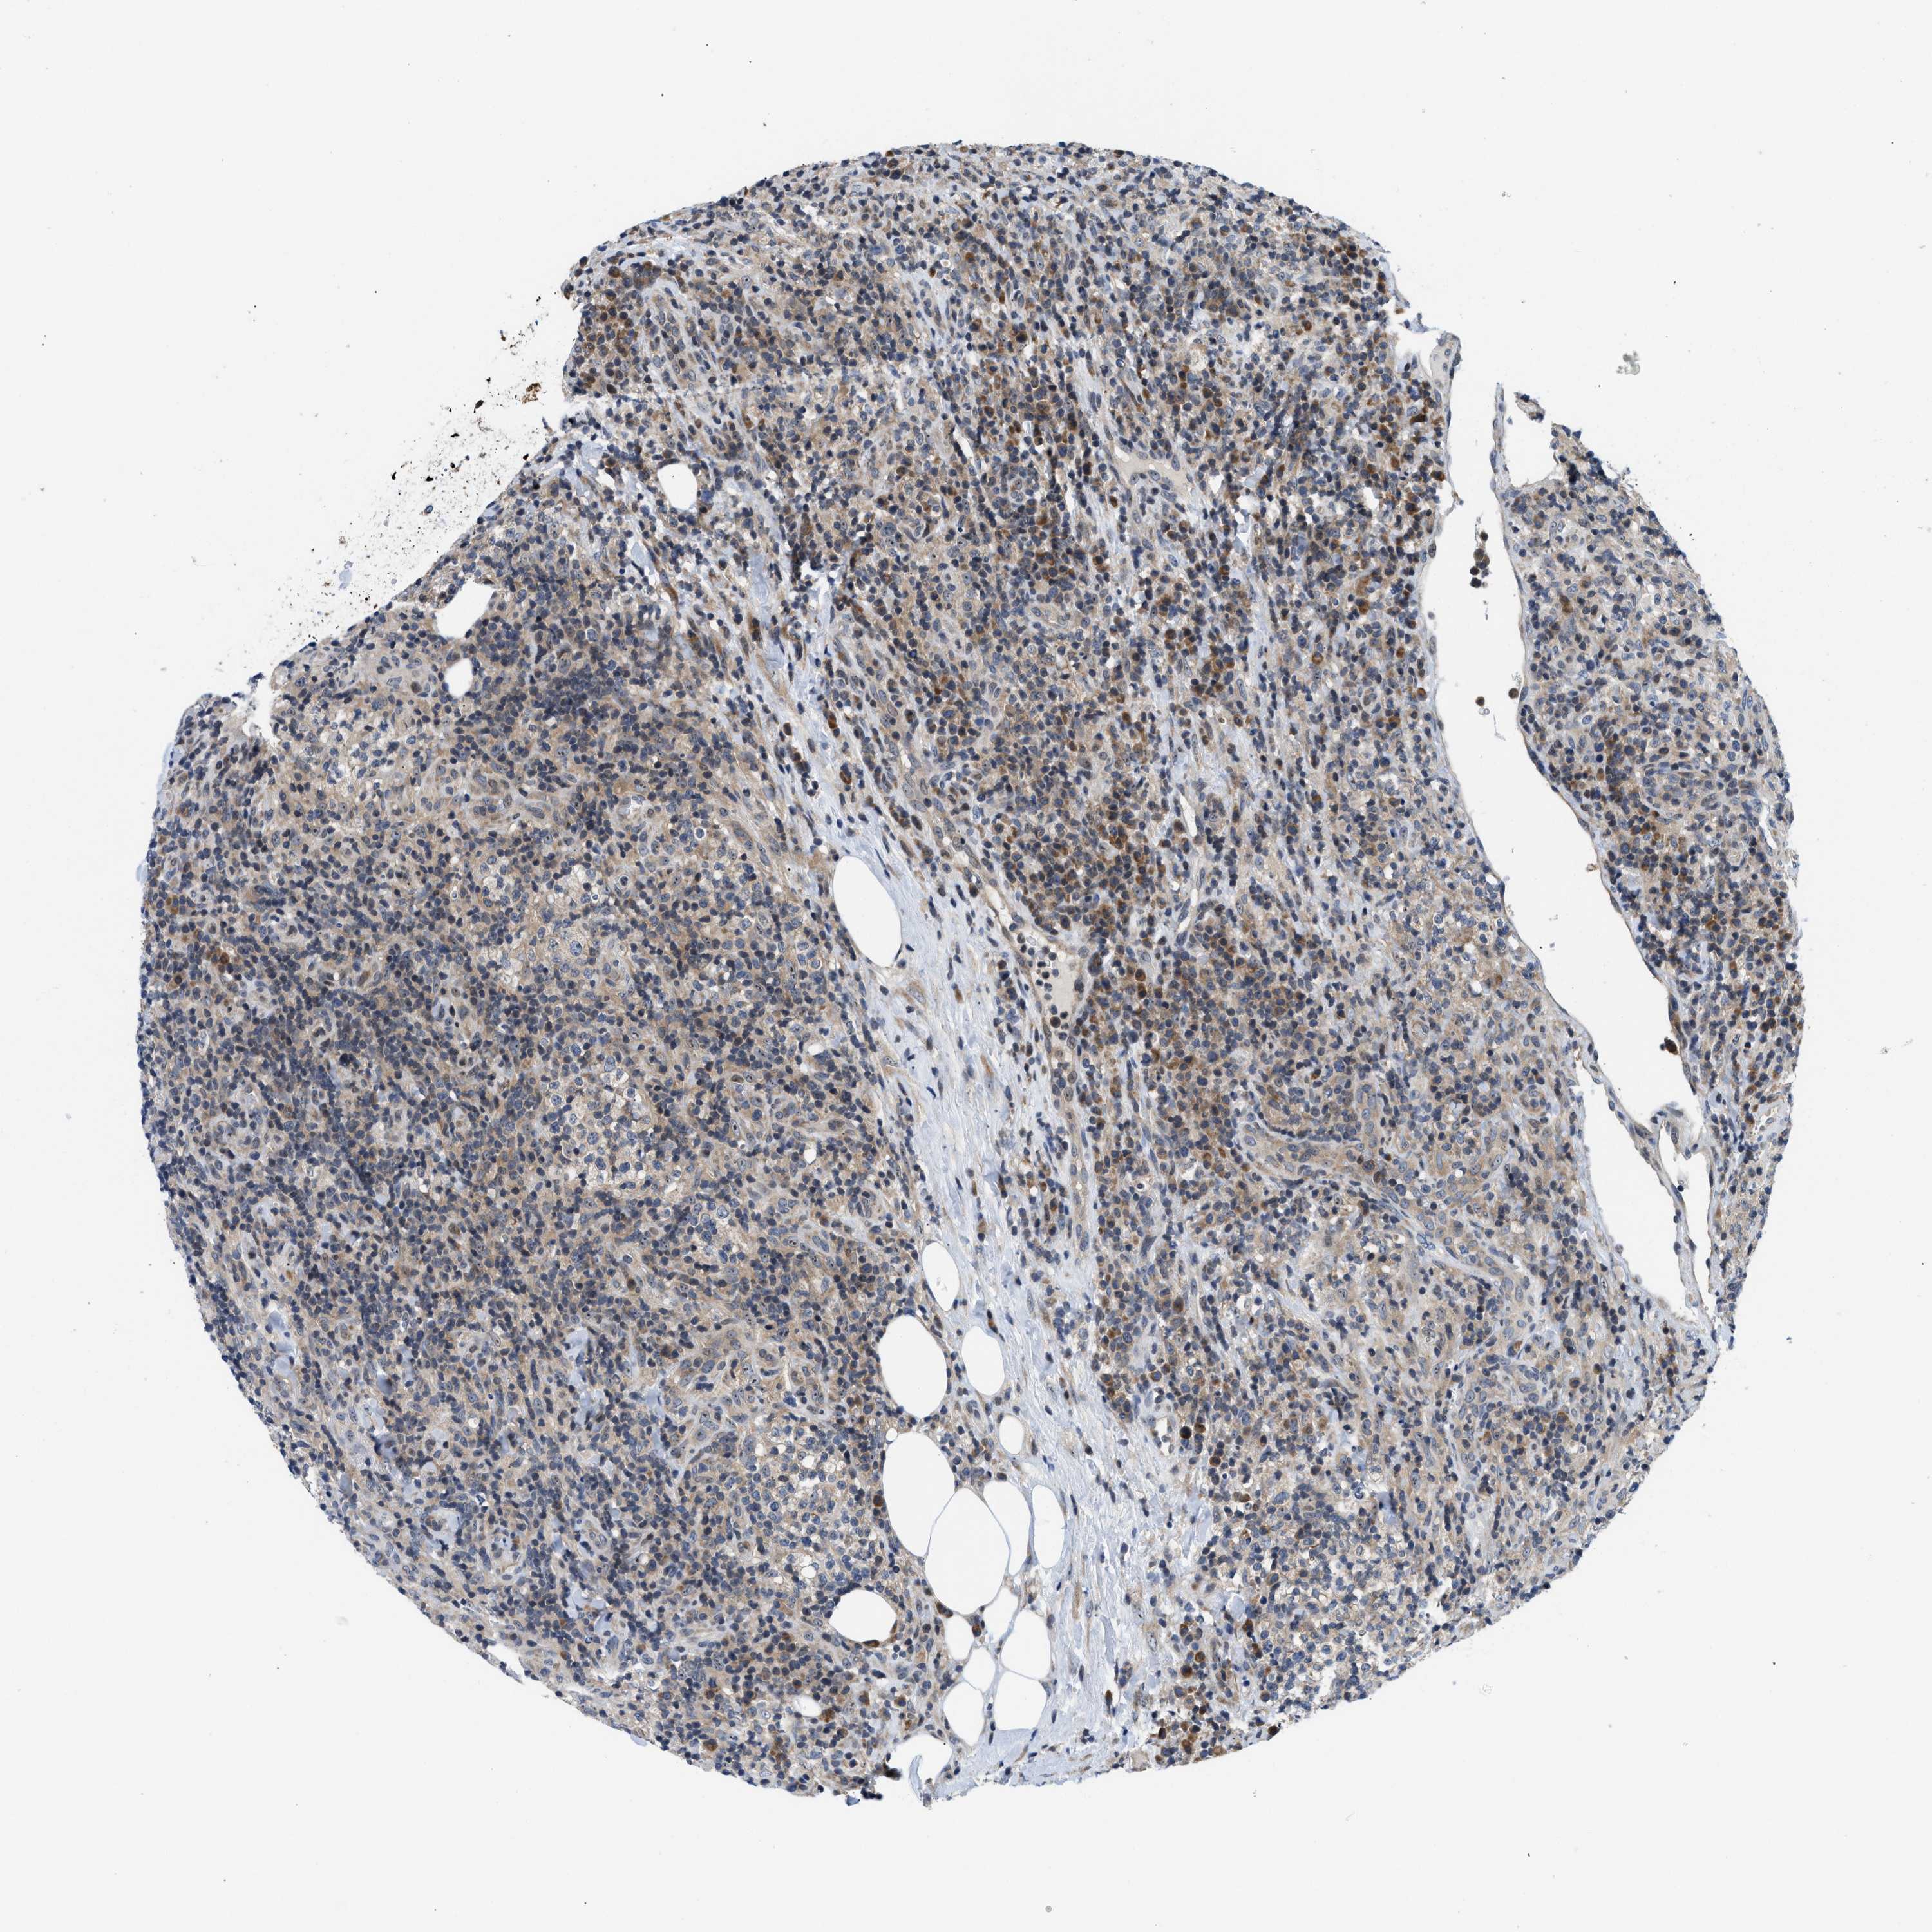

CANCER LYMPHOMA Show tissue menu

LYMPHOMA - Protein expressioni

A mouse-over function shows sample information and annotation data. Click on an image to view it in a full screen mode. Samples can be filtered based on level of antibody staining by selecting one or several of the following categories: high, medium, low and not detected. The assay and annotation is described here.

Antibody stainingi

Antibody staining in the annotated cell types in the current human tissue is reported as not detected, low, medium, or high, based on conventional immunohistochemistry profiling in selected tissues. This score is based on the combination of the staining intensity and fraction of stained cells.

Each image is clickable and will lead to virtual microscopy that enables deeper exploration of all samples and also displays staining intensity scores, fraction scores and subcellular localization as well as patient and tissue information for each sample.

Antibody HPA015788

Antibody CAB025983

Staining

High

Medium

Low

Not detected

Intensity

Strong

Moderate

Weak

Negative

Quantity

>75%

75%-25%

<25%

None

Location

Nuclear

Cytoplasmic/membranous

Cytoplasmic/membranous,nuclear

Hodgkin's disease, NOS

Malignant lymphoma, non-Hodgkin's type, High grade

Malignant lymphoma, non-Hodgkin's type, Low grade